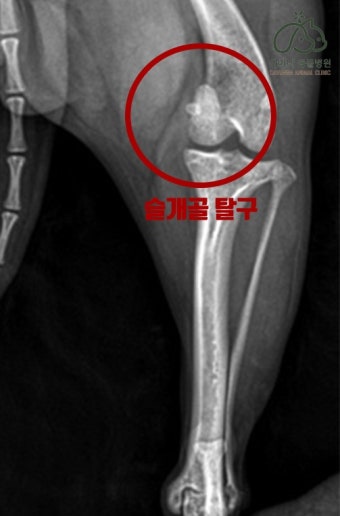

1. 슬개골 탈구란?

슬개골 탈구는 쉽게 말해 무릎뼈가 제자리를 벗어나는 증상입니다. 사람으로 치면 무릎이 '툭' 하고 빠지는 느낌인데, 강아지에게는 이게 지속적으로 반복될 수 있는 문제죠.

5. 단계별로 알아보는 슬개골 탈구 등급

| 1등급 | 슬개골이 간헐적으로 빠지지만 바로 제자리로 돌아감 |

| 2등급 | 빠지면 손으로 눌러야 돌아옴 |

| 3등급 | 대부분 탈구 상태이며, 가끔만 정상 위치 |

| 4등급 | 항상 탈구 상태, 무릎 관절이 고정되지 않음 |